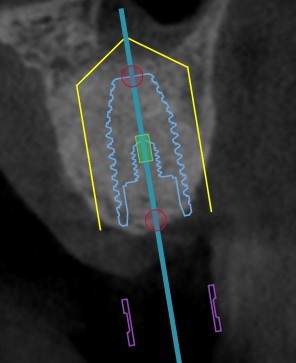

- d'une greffe au sein du bas fond sinusien maxillaire car la hauteur d'os sous ce sinus est insuffisante à la pose d''implant.

Pour la greffe du bas fond sinusien, l’incision se situe au niveau de la gencive. Puis on réalise une petite fenêtre osseuse en regard du sinus, on repousse délicatement la muqueuse sinusienne  et on positionne l'aggloméra de biomatériaux  et de plasma dans le sinus maxillaire.

Sinus Lift : greffe du bas fond sinusien